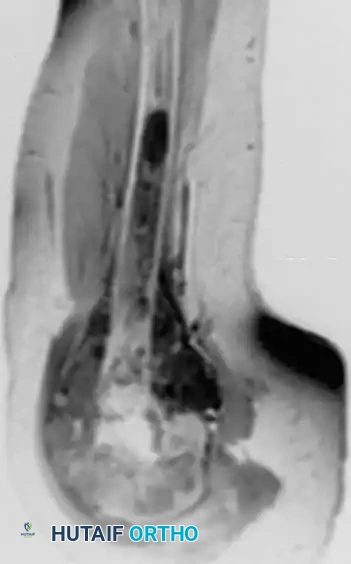

Anteroposterior view of the proximal humerus in an 8-year-old boy with osteoblastic osteosarcoma, alongside an MRI demonstrating the extensive intramedullary and soft-tissue involvement.

Magnetic Resonance Imaging (MRI): MRI of the entire involved bone is mandatory. It is the gold standard for determining the intraosseous extent of the tumor, identifying "skip metastases" (distinct tumor foci within the same bone), and delineating the relationship of the soft-tissue mass to critical neurovascular structures.